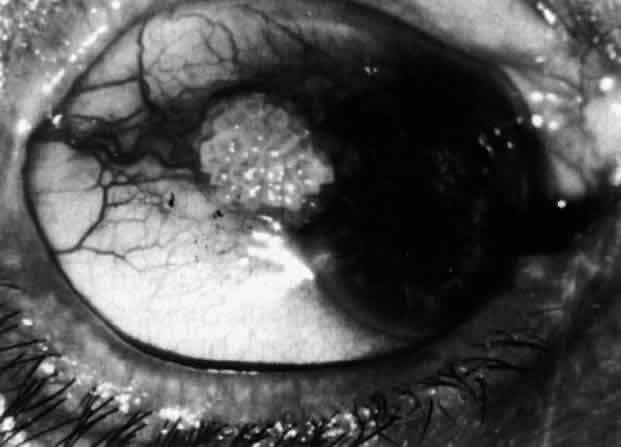

The object of slit lamp examination is to determine the depth and nature of scleral and episcleral conditions and the presence of corneal changes. The changes seen are drawn in the records. With the use of diffuse light with a neutral density filter, the vascular networks of both eyes are examined in detail to determine the layer in which the vessels show maximum congestion, the infiltration of episcleral tissues, and the edema of sclera, episclera, or subconjunctival space. Slit lamp examination is also used to ascertain the nature and depth of any corneal changes; the presence of scleral edema (for which it may be necessary to blanch the superficial tissues with epinephrine 1:1000 or phenylephrine 10%); the nature of any episcleral infiltration or mass; and the presence of cells in the anterior chamber or vitreous and posterior synechiae. The red-free (green) filter is extremely valuable in confirming the areas of maximum congestion and whether any areas are totally avascular. Because this is an important physical sign and is easily missed, examination in red-free light should be routinely performed. The green light brings the vessels into very sharp contrast with the background and enables the position of maximum inflammation to be determined with certainty. It also enables the paths and configurations of the vessels to be followed and will show lymphocytic infiltration of the episcleral tissue as yellow spots; this often indicates that the condition is more extensive than previously supposed (Fig. 8).

Fig. 8. Examination in red-free light. Blood vessels brought into sharp contrast reveal areas of lymphocytic infiltration in episcleral tissues, in this case due to herpes simplex virus.